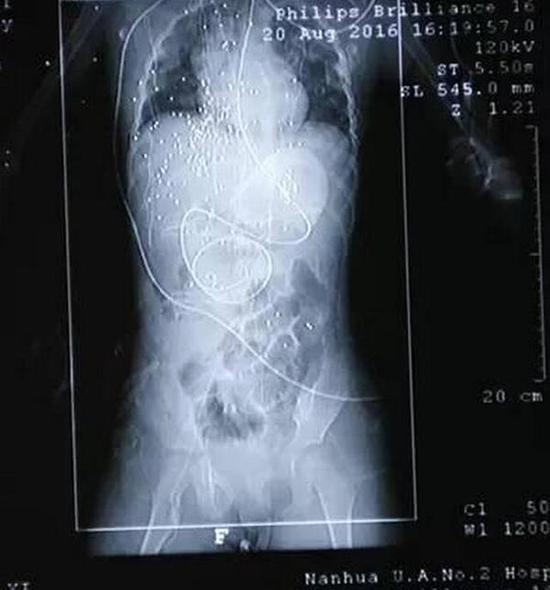

More than 100 bullets remain in the young girl’s body after a four-hour surgery. According to Huang Bin, a senior nurse at the ICU of Xiangya Hospital of Central South University, the girl’s gunshot wounds spread across her ribcage to her right arm and abdomen. The steel bullets also affected her heart and liver.

“The bullets are relatively small, and move even without much force. More surgery could cause additional damage to the child’s body. Some [of the bullets] can stay inside if they do not affect her organs,” Huang noted, adding that the girl is also being treated for tetanus in case any of the bullets cause the infection, the report explained.